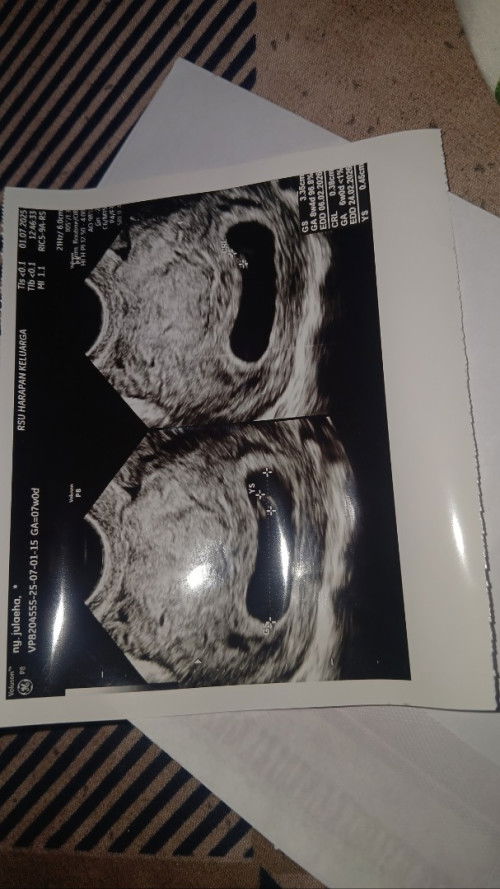

maaf mau tanya kali aja disini ada yang pernah ngalamin hal sama bun, aku baru USG transvaginal karna d USG 2D janin dan detak jantung ga keliatan pas Transvaginal Alhamdulillah semuaa terlihat jelas, kata dokter janinnya sehat. Tapi yang harusnya usia kandungan 7 week pas d USG baru 6 week, saya sangat kepikiran soalnya pernah ada riwayat keguguran 3 bulan lalu Ada yang pernah ngalamin hal yang samaa gaa bun tolong kasih sayaa semangat dan perhatian klo janin saya akan baik² sajaaa soalnya kepikiran bngttt takut terjadi hal kayak dlu🙏🥺#mohonbantujawabbunda